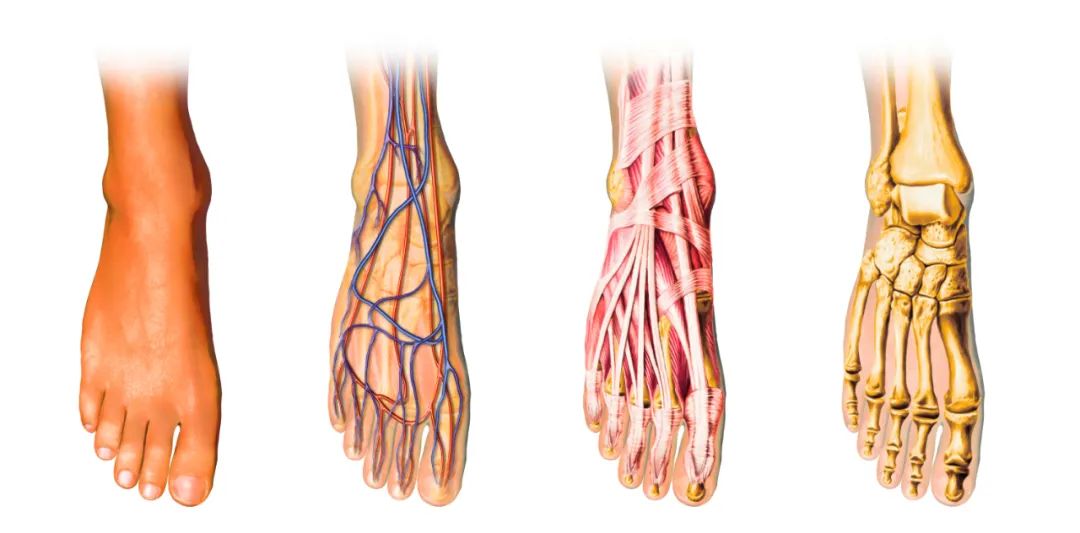

踝关节本身的结构并不复杂,无非就是胫骨以及腓骨的下端和距骨上端的关节面组成,但是对于医生来说如果要做踝关节骨折的手术,就非常复杂。

踝关节周围的韧带比较多(如:下跟距韧带、下胫腓联合韧带、三角韧带等等),伴随踝关节骨折的发生,这些韧带也常会出现不同程度的损伤。关节损伤加上韧带损伤,治疗起来就非常有难度。